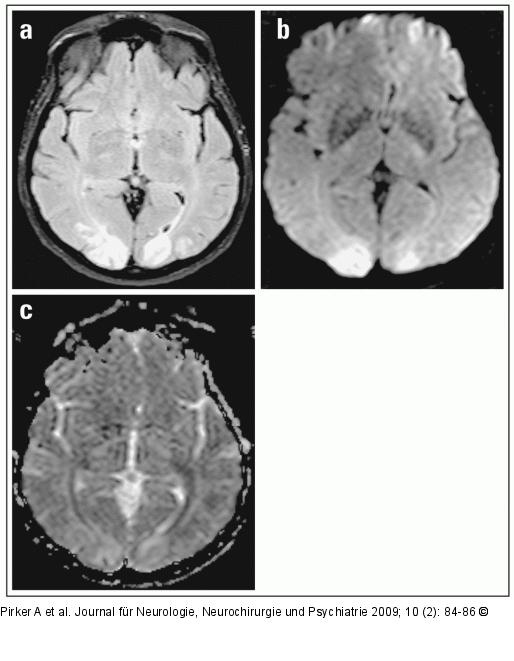

Abbildung 1: FLAIR-Sequenz (a) Axiale FLAIR-Sequenz, (b) axiales Isotropiebild (diffusionsgewichtet), (c) apparenter Diffusionskoeffizient: hyperintense Signalveränderungen beidseits im okzipitalen Kortex. Das MR-Erscheinungsbild auf den verschiedenen Sequenzen spricht für das Vorliegen eines vasogenen Ödems. |

(a) Axiale FLAIR-Sequenz, (b) axiales Isotropiebild (diffusionsgewichtet), (c) apparenter Diffusionskoeffizient: hyperintense Signalveränderungen beidseits im okzipitalen Kortex. Das MR-Erscheinungsbild auf den verschiedenen Sequenzen spricht für das Vorliegen eines vasogenen Ödems. |